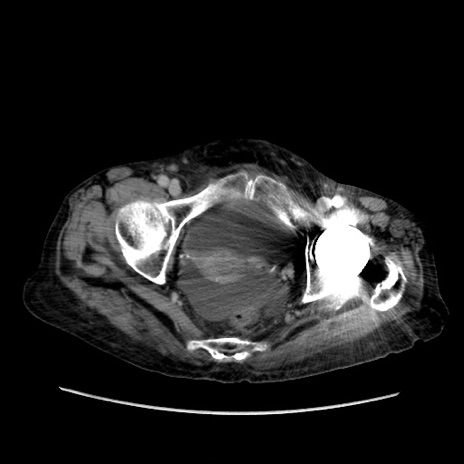

症例31(横断像)

【症例】80歳代 女性

【主訴】腹部膨満感

【現病歴】他院にて肝硬変にてフォロー中。1週間前から便秘、腹部膨満感、臍部腫瘤あり受診となる。

【既往歴】肝硬変

【身体所見】腹部膨隆あり、皮膚変化なし、疼痛なし。

【データ】WBC 4600、CRP 0.25